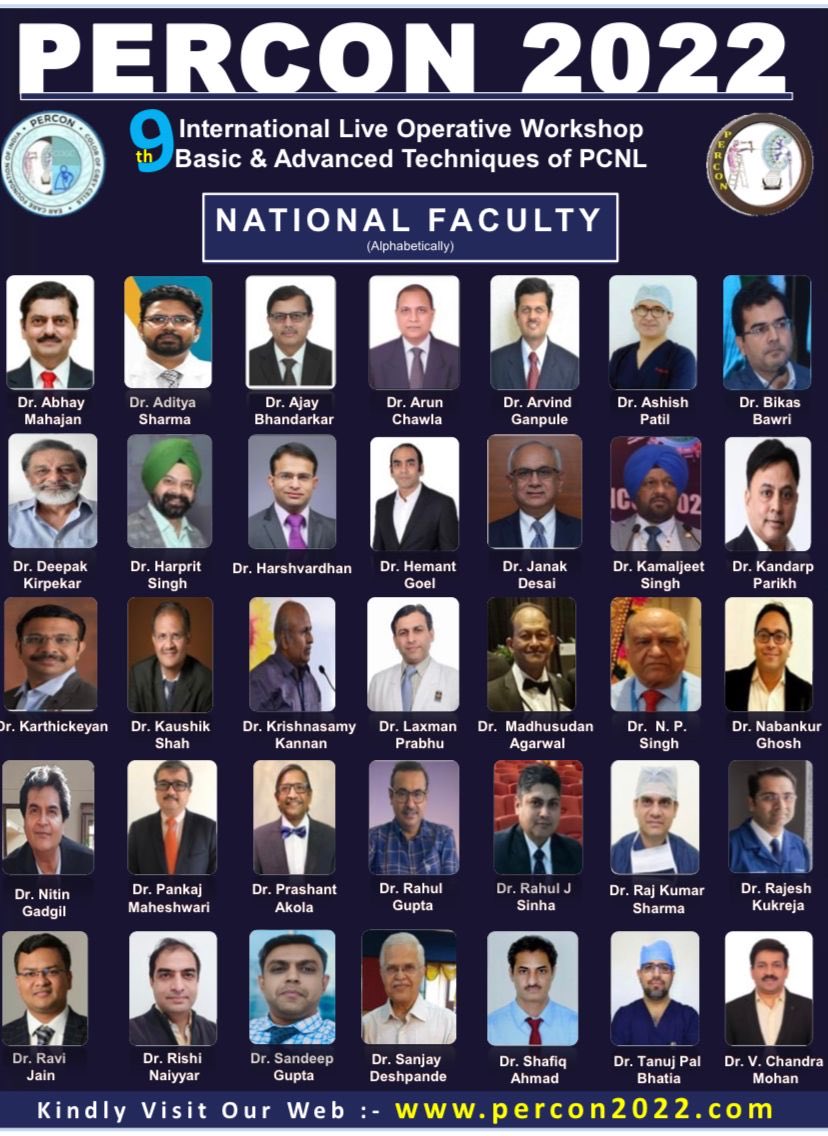

Amer. Urol. Assn. Kelly Swords, MD, MPH, FACS Laura Bukavina May, I request every interested urosurgeon to get registered at the earliest. In view of previous experience of overcrowding. PERCON IS OPEN ONLY FOR UROLOGISTS. You are welcome to send any suggestions for improvements. percon2022.com

Get ready for PERCON 2024.. The largest event focussed on PCNL worldwide.. every aspect of PCNL is discussed threadbare.. Shashi Kiran Pal Endourology Academy Dr Ashish Rawandale Patil Dr Avreen Singh Shah MCh MS mohamed elshazly Dr Vaddi Chandra Mohan Karthickeyan N 𝘿𝙚𝙚𝙥𝙖𝙠 𝙍𝙖𝙜𝙤𝙤𝙧𝙞 Abhay Mahajan Dr. Pankaj N. Maheshwari